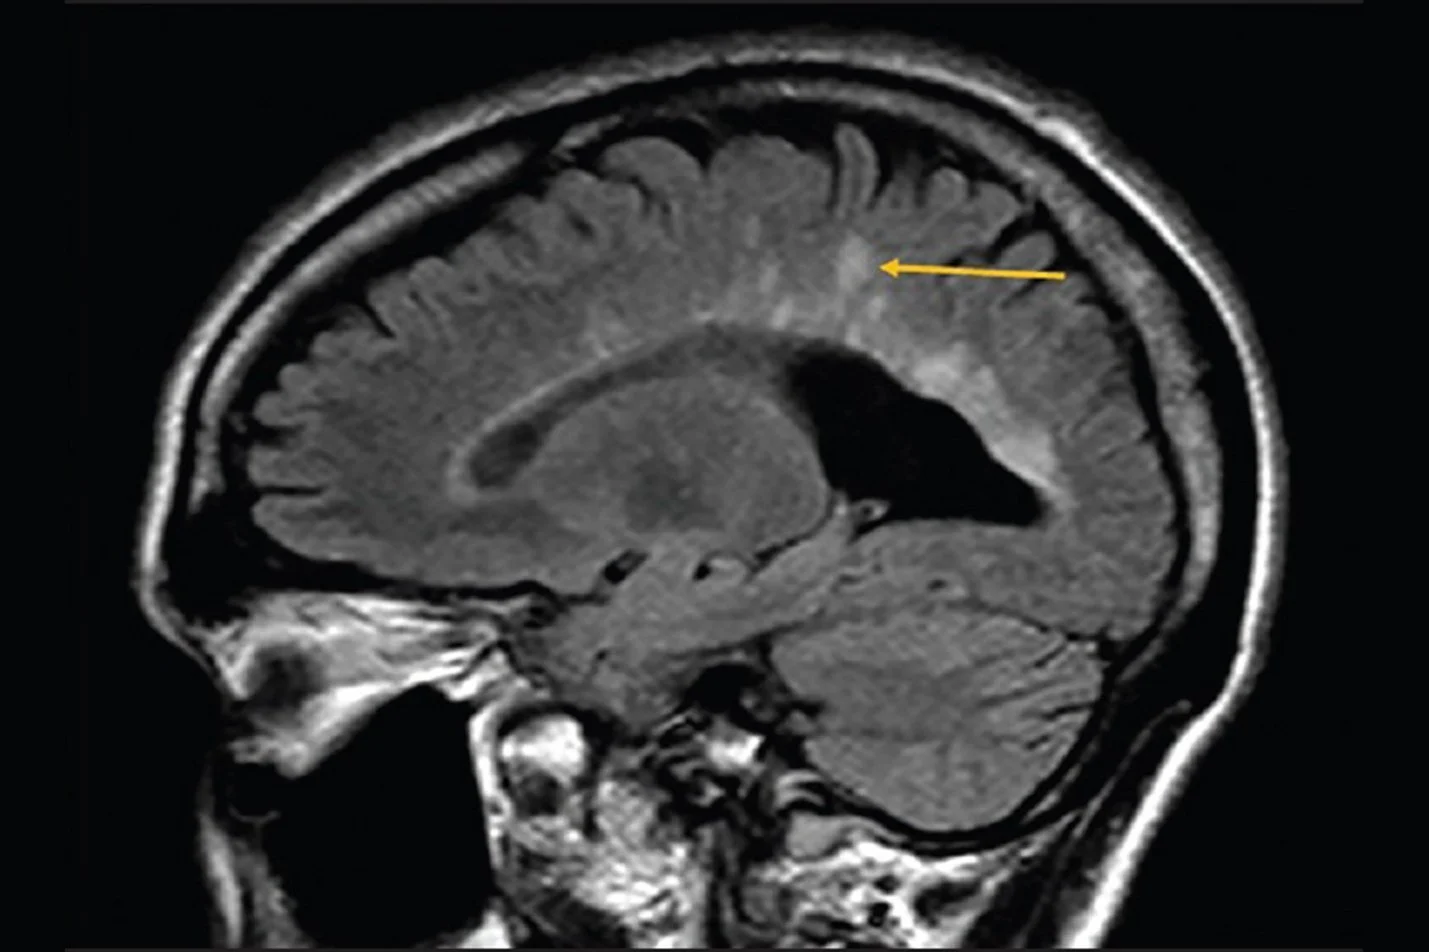

Here is an Example of Dawson’s Fingers

Reference:​What Are Dawson’s Fingers And What Do They Reveal About MS?

From Health Central: (August 1, 2025) “These finger-shaped brain lesions are a key clue in the hunt for a MS diagnosis.”Authors: Barbara Williams Cosentino, LCSW and R. N. Elizabeth Millard – the Medial Reviewer; Jason H. Lin, M.D., Neurologist

“An arrow points to “Dawson’s fingers” on an MRI of a person with multiple sclerosis”

From “Annals of Indian Academy of Neurology

Credit: Health Central